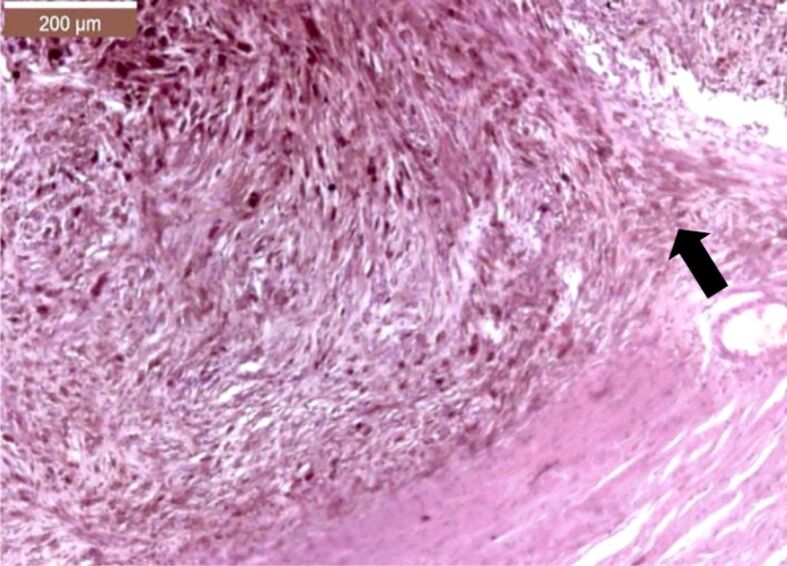

Ocular melanoma is a rare but complex disease in current medical practice. Our retrospective study spans over a period of 28 years and analyzed uveal and conjunctival melanomas that were consecutively admitted, diagnosed, and treated in the 2nd Ophthalmology Clinic of Prof. Dr. Nicolae Oblu Emergency Clinical Hospital, Iaşi, Romania. The patients were selected from the records of the Department of Pathology of our Hospital, being diagnosed by standard histopathological techniques. The aim of this study was to summarize the epidemiological and pathological aspects of uveal and conjunctival melanomas in Northeastern region of Romania. In our study, we did not notice a predilection of uveal and conjunctival melanoma to one particular gender. The most common histological subtypes of ocular melanomas were the heavily pigmented spindle cell subtype, followed by the epithelioid subtype. Our patients sought medical help in a timely manner, before the systemic invasion of the disease could develop.

Abstract Image